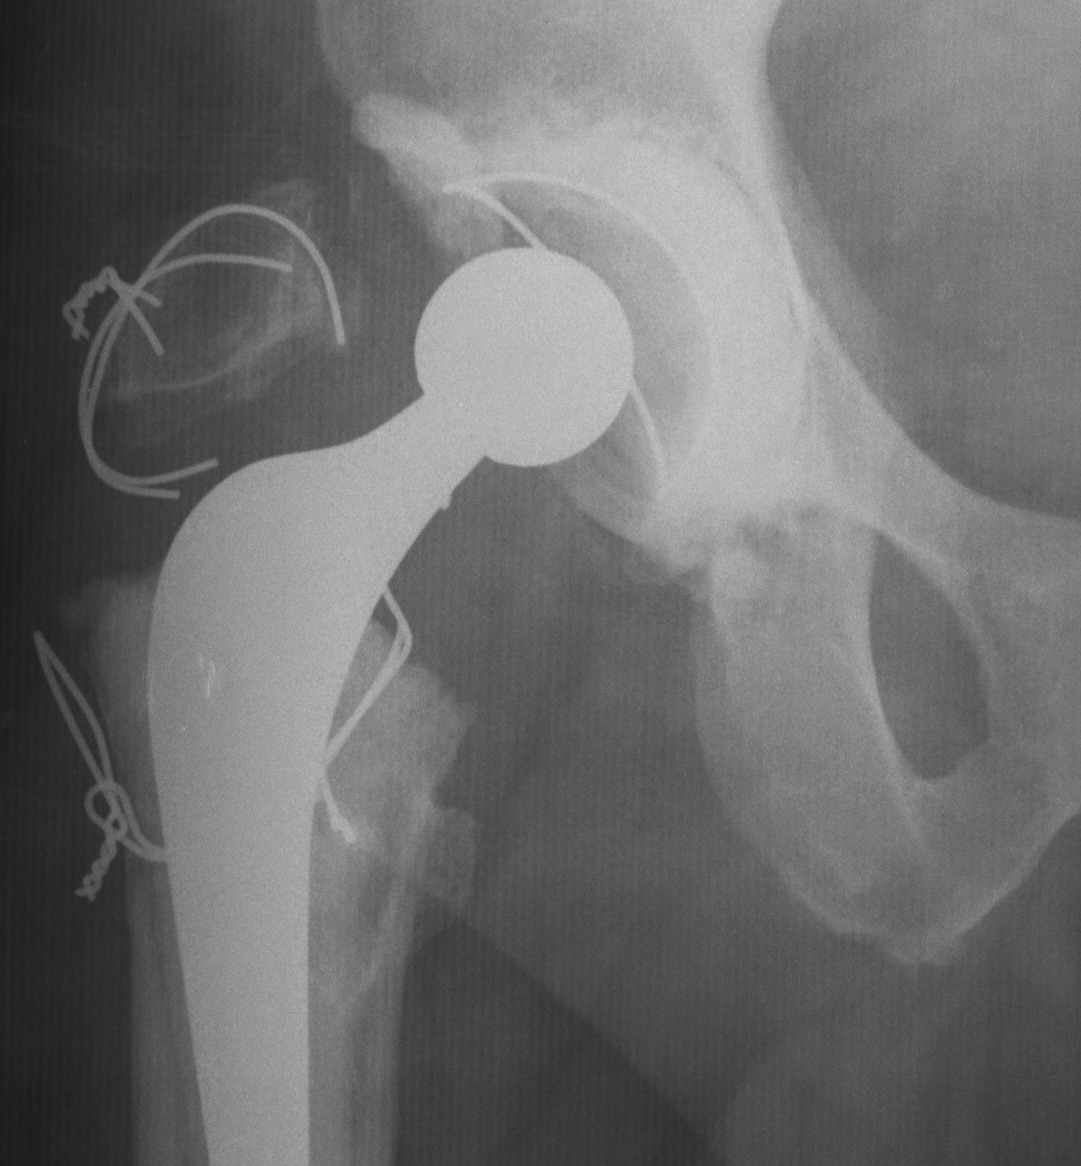

Standard Trochanteric osteotomy

Concept

- detach GT with only abductors attached

Fixation

- 3 - 4 intraosseous wires

- claw plate

Modification / Chevron Osteotomy

- increased stability

- decreased non union